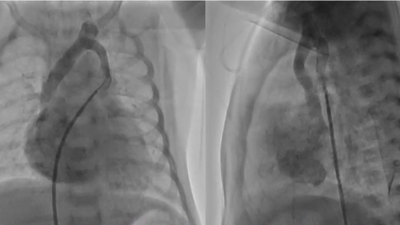

Fig. 2 (A) Angiography showing the levoatrial cardinal vein draining to the innominate vein. (B) 3D contrast-enhanced computed tomography viewing from the front illustrates the levoatrial cardinal vein connecting the left pulmonary vein to the innominate vein. (C) 3D contrast-enhanced computed tomography viewing from the left-posterior aspect shows the levoatrial cardinal vein connecting the left pulmonary vein to the innominate vein.

Red arrows indicate the levoatrial cardinal vein.